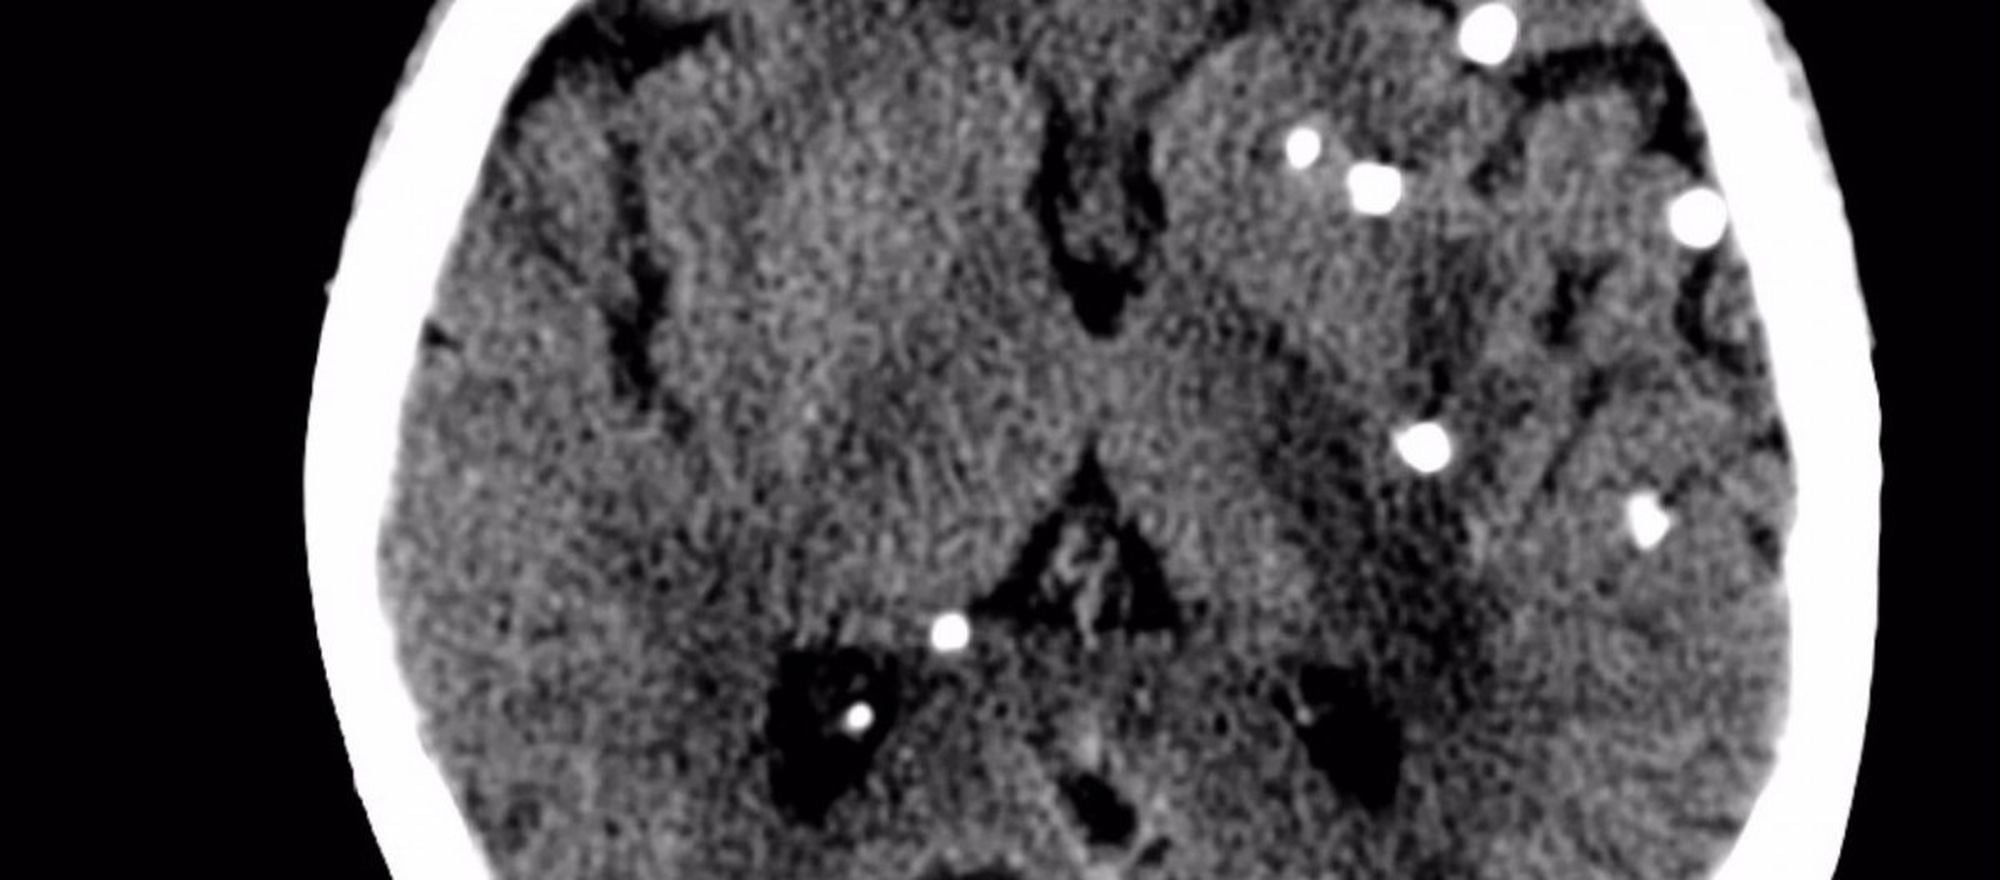

Eğer herhangi bir normal beyin MRI fotoğrafı gördüyseniz, uzman olmasanız bile, bu fotoğrafta gördüğünüzde bir anormallik olduğunu hemen anlayabilirsiniz. Evet, o beyaz noktalar bir "sorun"a işaret ederler. Ancak hayır, akla gelen ilk şey olan "kanserli doku" ya da "tümör", bu beyaz noktaların sebebi değildir. O beyaz noktalar, afiyetle beyin dokunuzdan beslenen ve burada büyüyen domuz tenyası larvalarıdır! Yani beyninizde yaşayan bir çeşit solucan...

Sistiserkoz, genel olarak domuz tenyası olarak bilinen Taenia solium türü tarafından dokuların enfekte olmasıyla karakterize edilen hastalıktır. Ancak bu tenya, özellikle beyne yerleştiğinde nörosistiserkoz denen hastalık oluşur. Bu hastalığa sahip insanlarda yıllar boyunca hiçbir semptom oluşmayabilir ve tenyalar vücut içerisinde rahatça büyüyerek güçlenebilirler. Bu süre zarfında bir domuz tenyası 1-2 santimetre boya ulaşabilir. Bu tenyalar nihayetinde yeterli boyuta ulaştığında artık dokuda şişmelere ve bozulmalara neden olurlar ve bireyde nöbetler görülmeye başlar.

Daha dehşet verici 2 bilgi verilebilir. Bunların ilki şudur: bu tenyalar vücudunuzda 1-2 tane bulunmazlar. Genelde bir defa bulaşma gerçekleştiğinde yüzlercesi ve hatta kimi zaman binlercesi vücudunuza yayılırlar. Neyse ki bunların neredeyse hepsi vücudunuzdan atılır. Ancak bazıları gereğinden fazla büyüktür (veya belli evrimsel avantajlara sahiptirler) ve vücudu konak olarak belleyerek büyümeye başlarlar. Kan akışına karışarak vücudun herhangi bir yerine ulaşabilirler ve burada büyürler. İkinci dehşet verici bilgi ise, umulanın ve sanılanın aksine bu tenyaların hiç de seyrek olmayışıdır. Tam tersine, modern dünyada sinir nöbetlerinin 1 numaralı sorumlusu bu solucanlardır.